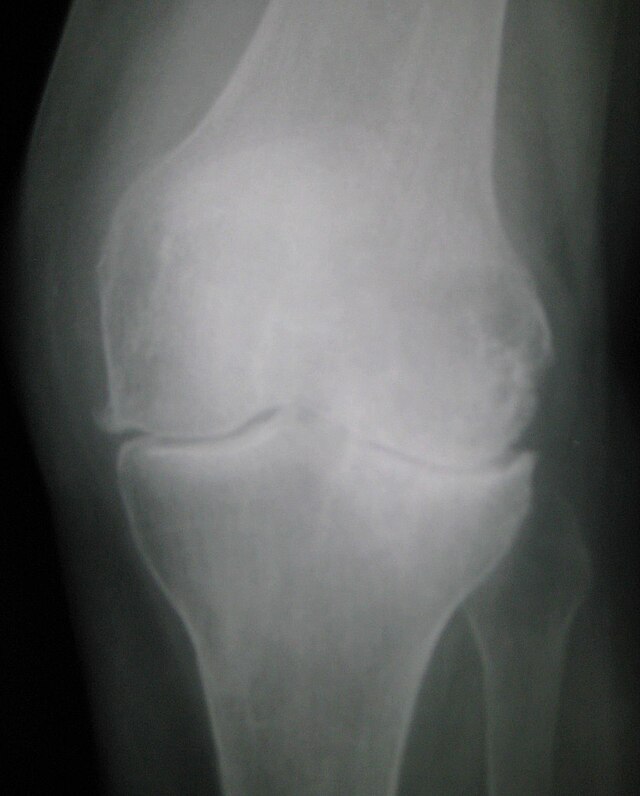

Artroz